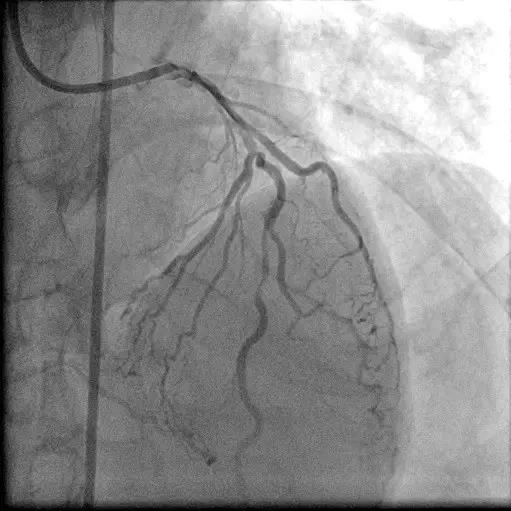

右冠闭塞

尝试PCI

桥血管